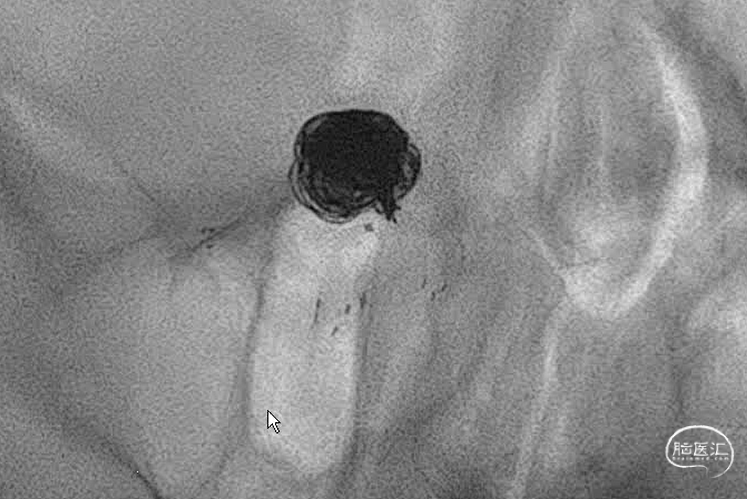

右侧大脑后动脉导管到位,解释一下由于远端血管条件不是太好,因此没有往更远走一些,二则,支架为无头的因此,此位置够用了。

因为在同侧所以也把弹簧圈微导管到位。虽然塑型角度比较大,可能由于血管的束缚和导管的回弹,角度感觉还是小了些,不过应该还是可以的。不过再上第三个管时,应该把前两个管锁紧。

第一个圈盘的还可以,直接支架辅助,一切都很顺利。微导管头的位置按原计划可行。

第一个圈填完,成型不错,弹簧圈微导管由于圈的张力作用,稍好低了一下头(红色标记),不过还好。